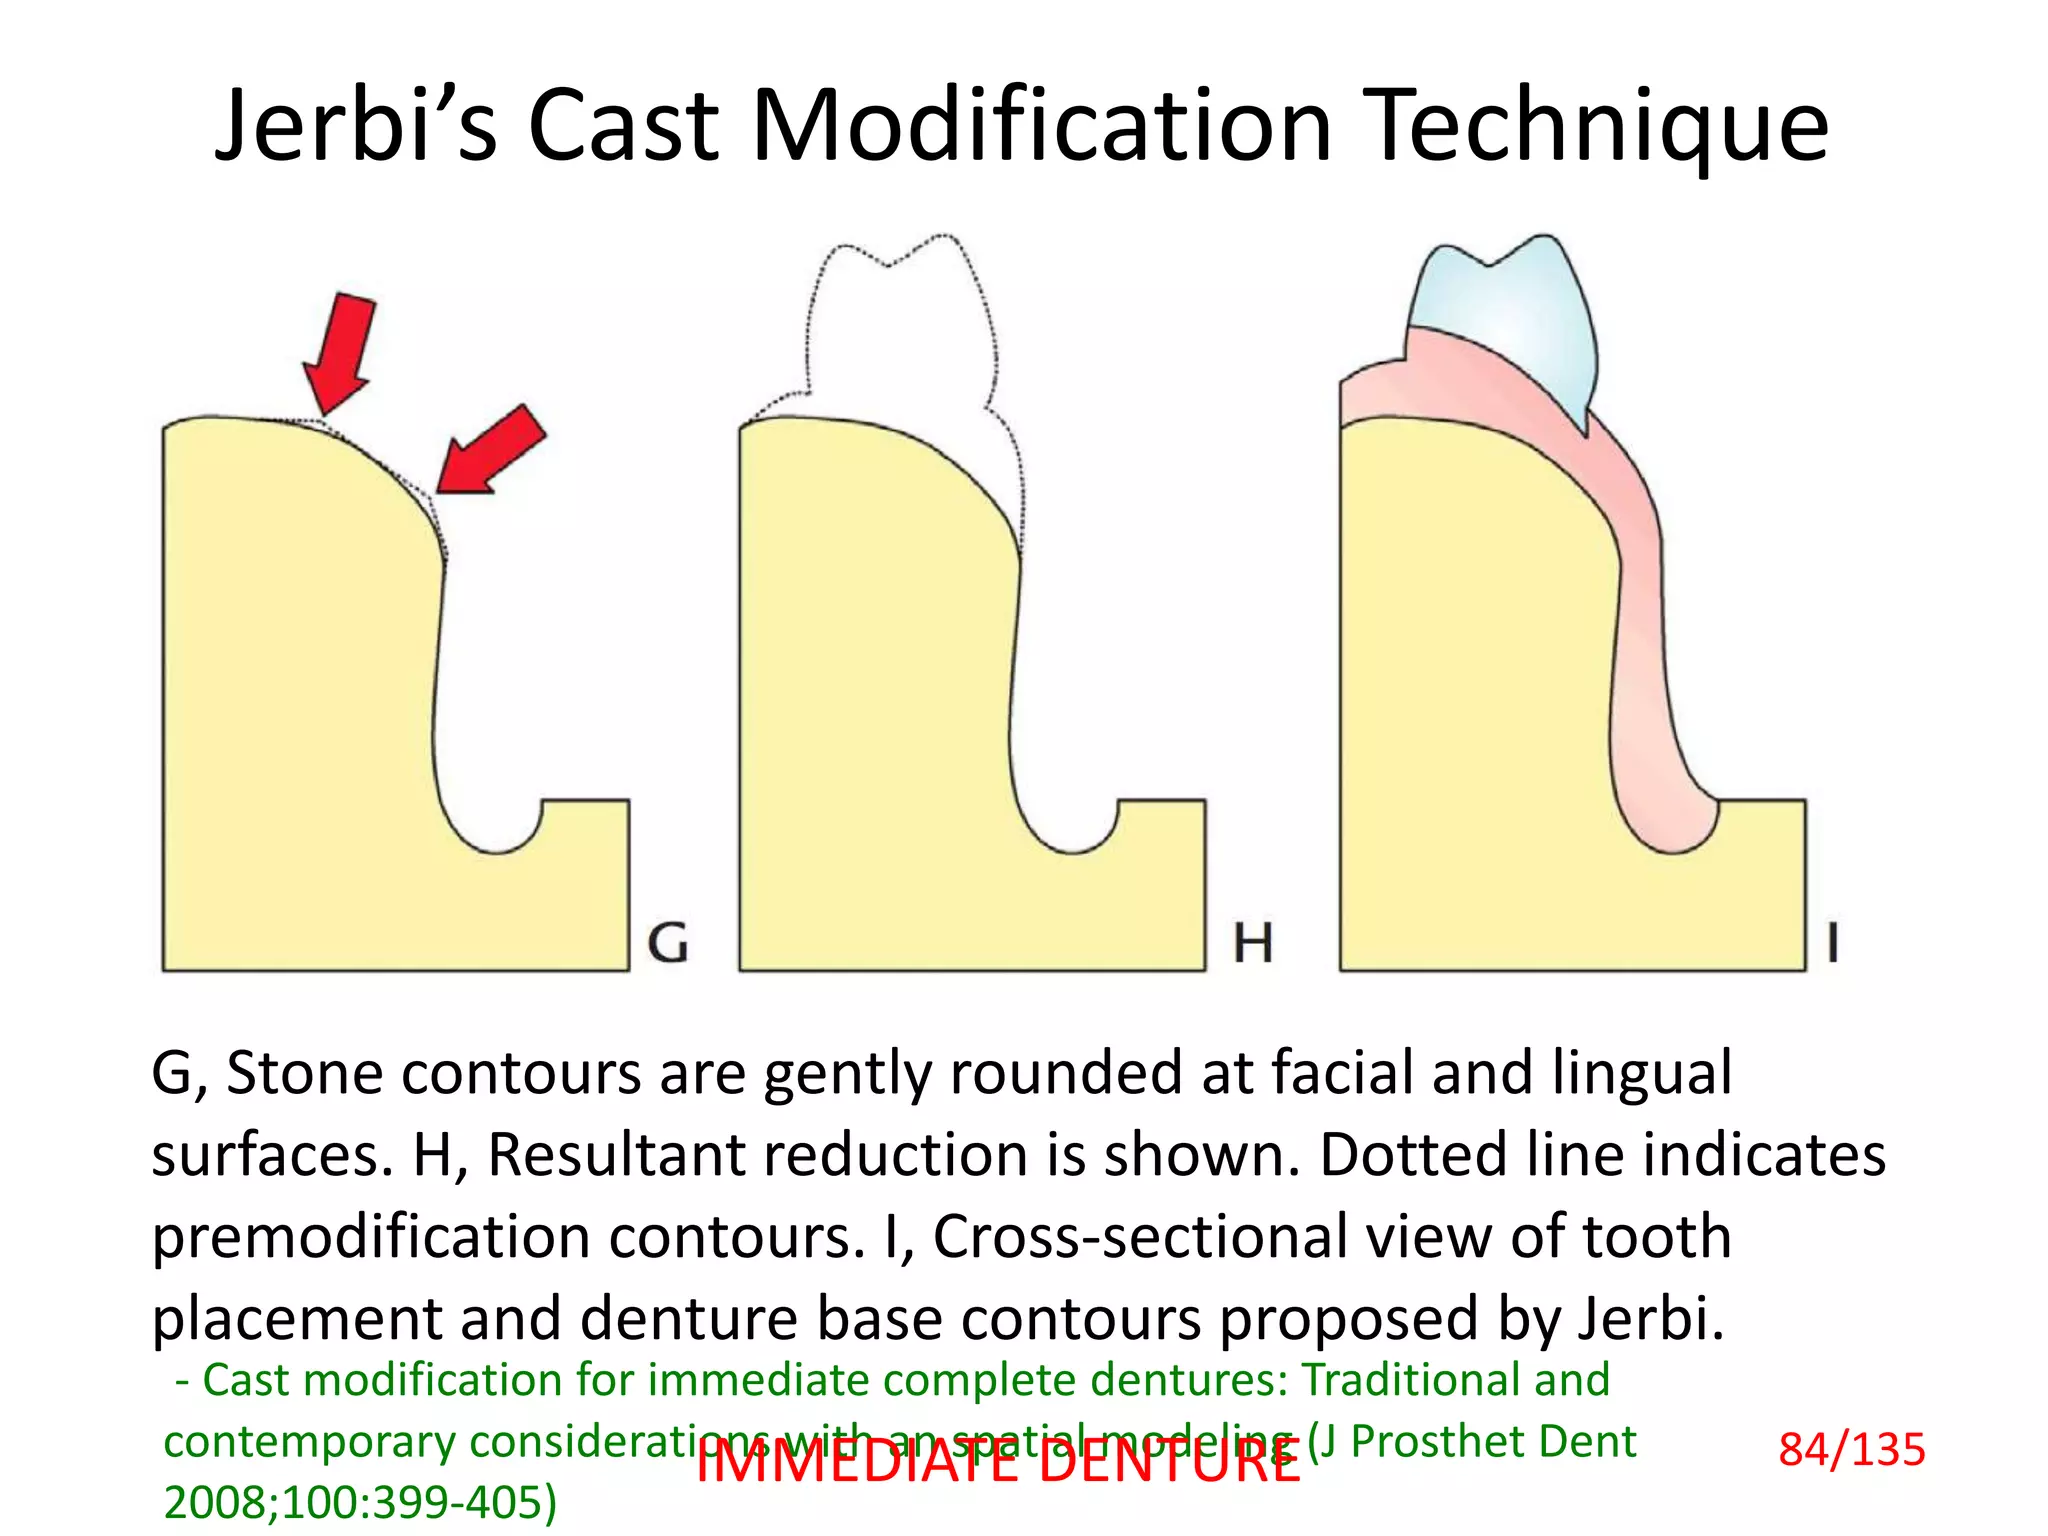

![DRAWBACK

Overzealous reduction at the facial, lingual, and

interproximal .

Denture bases would “bind” in these areas during

placement preventing complete seating of denture bases,

and necessitated adjustment of the denture bases, the

supporting hard and soft tissues, or both.

]IMMEDIATE DENTURE

- Cast modification for immediate complete dentures: Traditional and

contemporary considerations with an spatial modeling (J Prosthet Dent

2008;100:399-405) 86/135](https://image.slidesharecdn.com/t3lncoaotqgqautovoo0-signature-11bfc635dadd10a3a09f0305d36d2634b5c4d35ec2e6d3761fabe8171afe7f12-poli-160505064926/75/Immediate-Denture-86-2048.jpg)